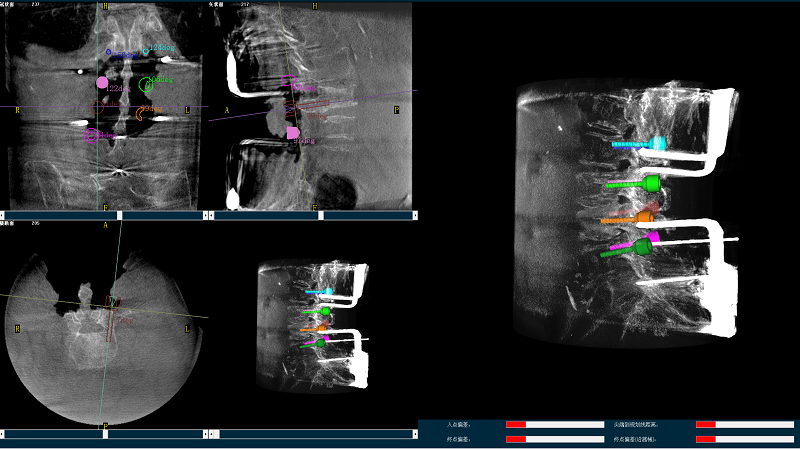

三维图像

(2)使用普爱医疗平板三维C形臂扫描患者,得到术中三维图像并传送至骨科机器人导航系统。骨科机器人导航系统基于高清术中三维图像进行手术规划。

手术规划图像